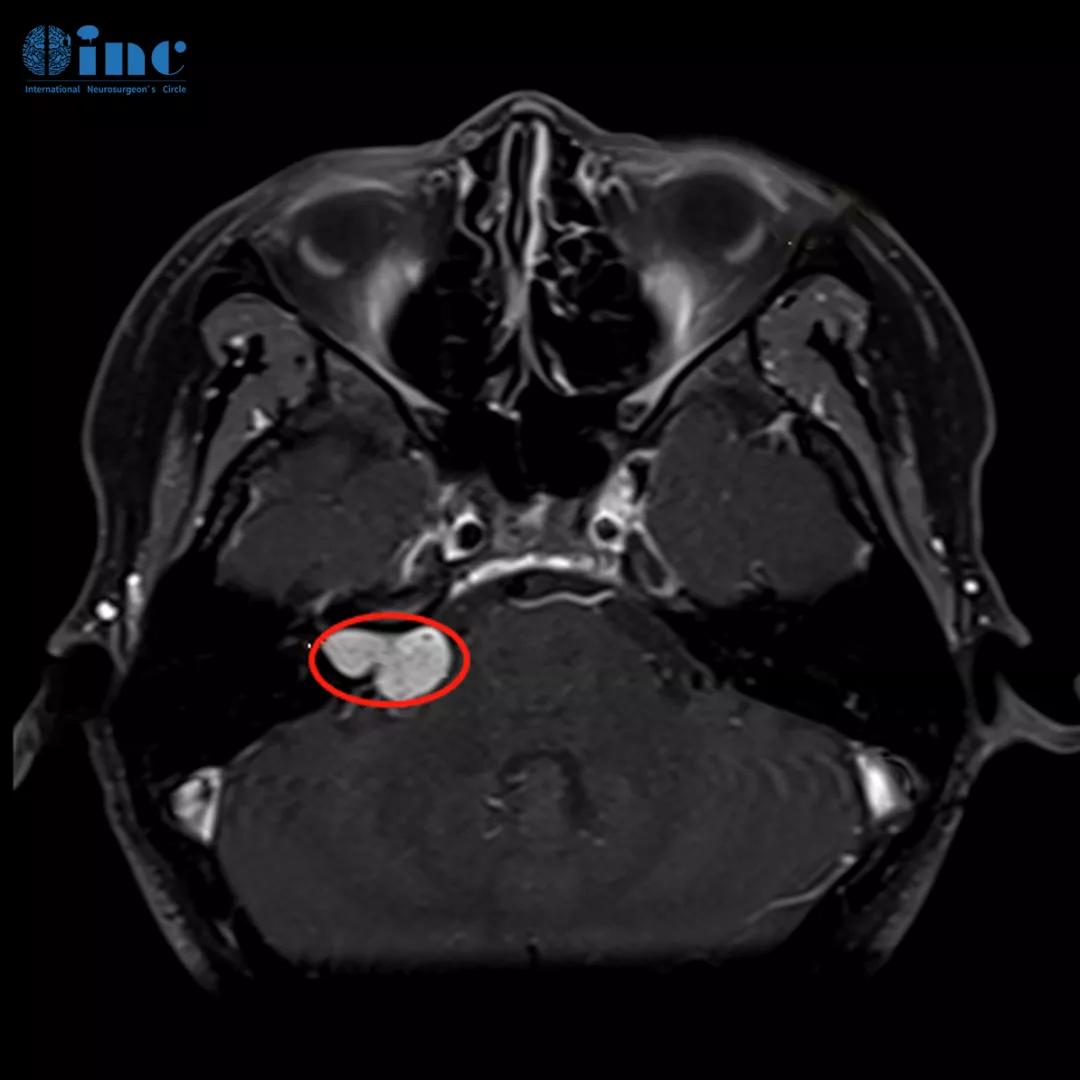

术前MR:姜女士颅脑MR提示听神经瘤病变,瘤体约2cm大小,但是有一部分完全生长于内听道骨质,压迫面听神经。

姜女士术前术后影像对比